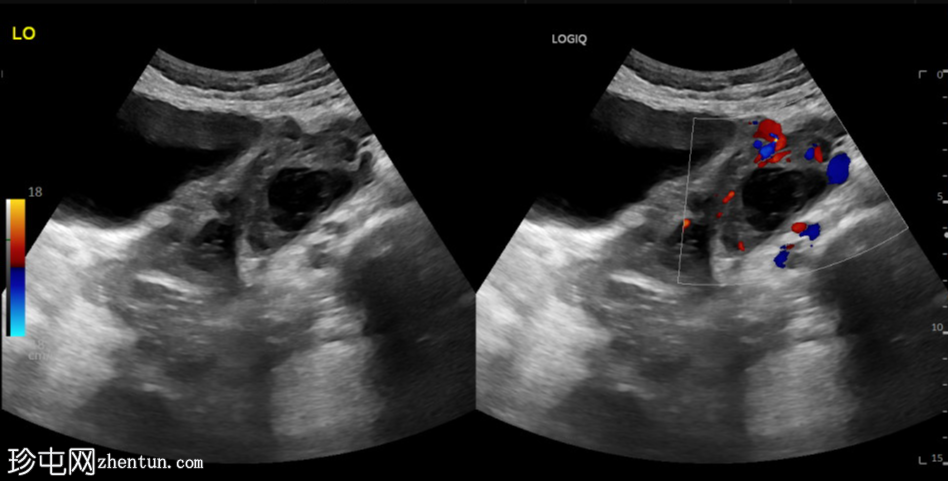

斜切面

左侧卵巢明显增大,可见一囊肿,大小约3.2 x 2.3 cm,呈火环征,可能为黄体囊肿。左侧卵巢与子宫之间可见一管状结构,直径约1.3 cm,内含浑浊液体,未见血管,最可能为输卵管积血。以上特征提示可能为左侧异位妊娠。

未见宫内妊娠囊。